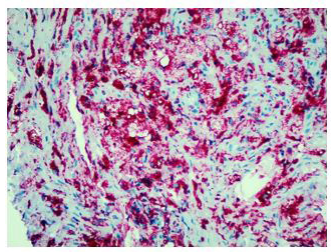

Finally, percutaneous CT-guided needle biopsy of the perirenal tissue was performed. Histological examination of the sample and IHC documented the presence of fibrous tissue with infiltration of foamy histiocytes containing lipids, with weak positive staining for S-100 and reactive for CD68, consistent with the diagnosis of ECD IHC showed BRAF cytoplasm reactivity of uncertain significance.

Histologically, xanthogranulomatous or xanthomatous infiltration of the tissue by foamy histiocytes can be detected, with immunohistochemistry (IHC) positive for CD68 and CD163 and negative for CDIa [8].

In fact, the imaging examinations performed during the last hospitalization showed a multiorgan involvement, in. duding coated aorta, hairy kidney. long bone thickening lesions, that lead us to consider a systemic disease. All that findings were consistent with the diagnosis of ECD, which was further corrob- orated by the histological finding of foamy histiocytes containing lipids reactive for CD68.